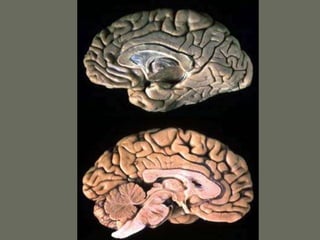

Gyruses and sulci

• Each lobe is composed of gyruses

separated by sulci